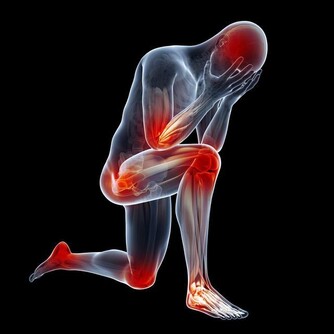

痛風的確是一種令病人非常痛苦的一種病症,當它發作的時候,可以說是「痛不欲生」,這種毛病還真會整人,它發作時間通常是選擇在夜深人靜的時刻。青木瓜泡茶加新鮮椰子汁:痛風再見了!